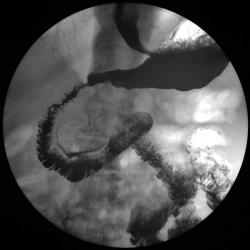

Пищевод.

дивертикулы пищевода

Изображение  Изображение